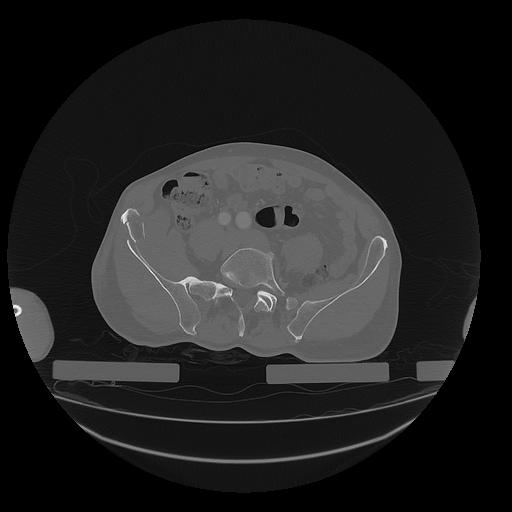

31 PULMON,CE,Vol,1.0,PULMON,,